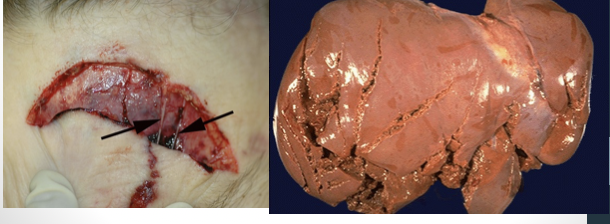

brick-red, large edema fluid, white hemorrhagic foam in trachea, subpleural hemorrhages (paltauf’s spots)

hemorrhage of mastoid bones or petrous portion of temporal bone

List the expected gross findings associated with drowning.